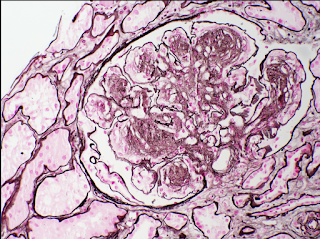

Monoclonal immunoglobulin deposition disease (MIDD) can shows nodules. They stain with PAS and silver stains (see image) and have refractile, PAS-positive deposits in the TBM too. IF is characterized by linear deposits along GBM & TBM with kappa>lambda deposits in LCDD (light chain variant) and IgG in HCDD (heavy chain). EM shows powdery deposits in inner GBM, outer TBM and in the nodules.